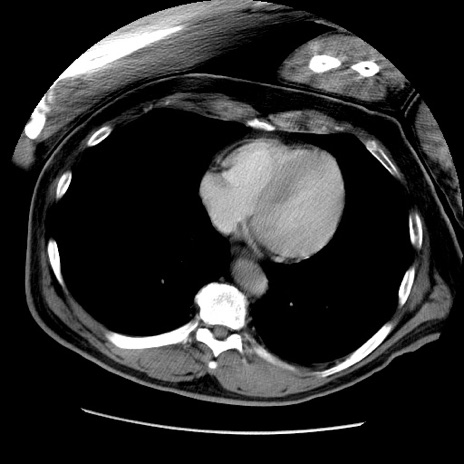

症例22(横断像)

【症例】50歳代男性

【主訴】腹痛

【現病歴】AVMからの被殻出血のため回復期リハ病棟入院中。 本日午後3時頃急に下腹部痛が出現した。

【既往歴】AVM、被殻出血、虫垂炎、高血圧

【身体所見】意識晴明、左半身不全麻痺、会話の理解は良好、36.5°C、腹部:膨隆、全体に板状硬、下腹部正中に圧痛点あり、反跳痛-、筋性防御不明、右下腹部にope scar

【データ】WBC 9400、CRP 0.06